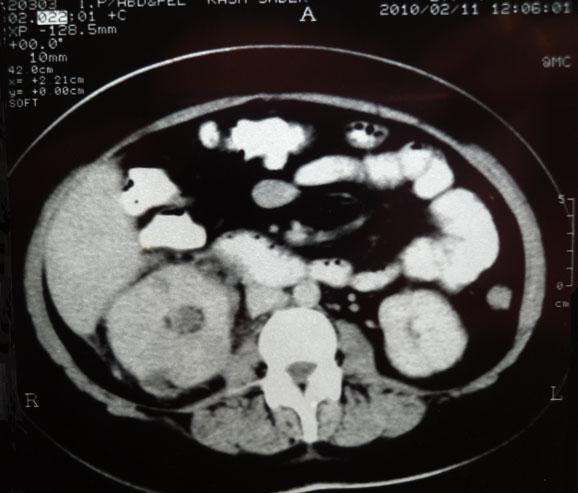

Chronological Photo-sequence

of the case progression

-After 2 months of presentation and treatment: